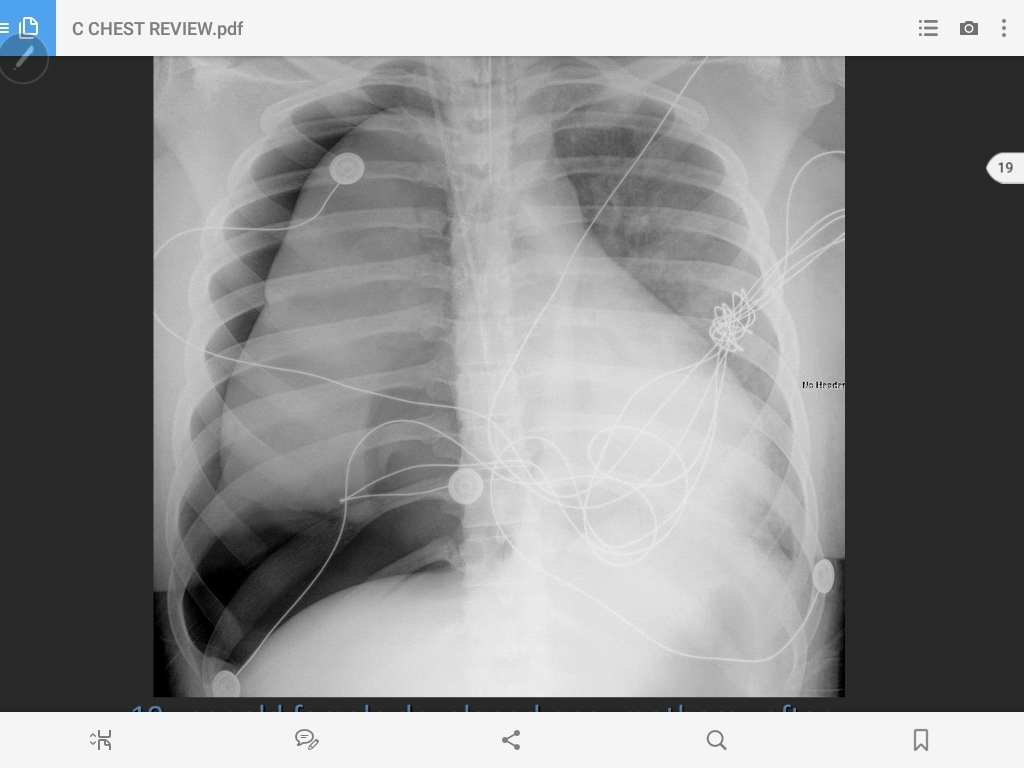

hiatal hernia